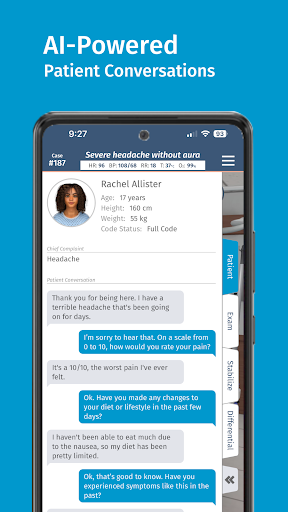

• AI của bệnh nhân cho phép thực hành với việc ghi lại bệnh sử

— Bệnh nhân AI —

Chúng tôi rất vui mừng được giới thiệu Bệnh nhân AI — tính năng hội thoại bệnh nhân mới của chúng tôi tận dụng những tiến bộ mới nhất trong trí tuệ nhân tạo. Các cuộc hội thoại AI của bệnh nhân là không giới hạn đối với người đăng ký Pro và khả dụng trên cơ sở hạn chế đối với người dùng Cơ bản và người dùng miễn phí.